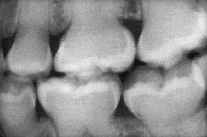

Right BW radiograph Katrina M (courtesy of Dr. BM Cleghorn, Dalhousie University).

|